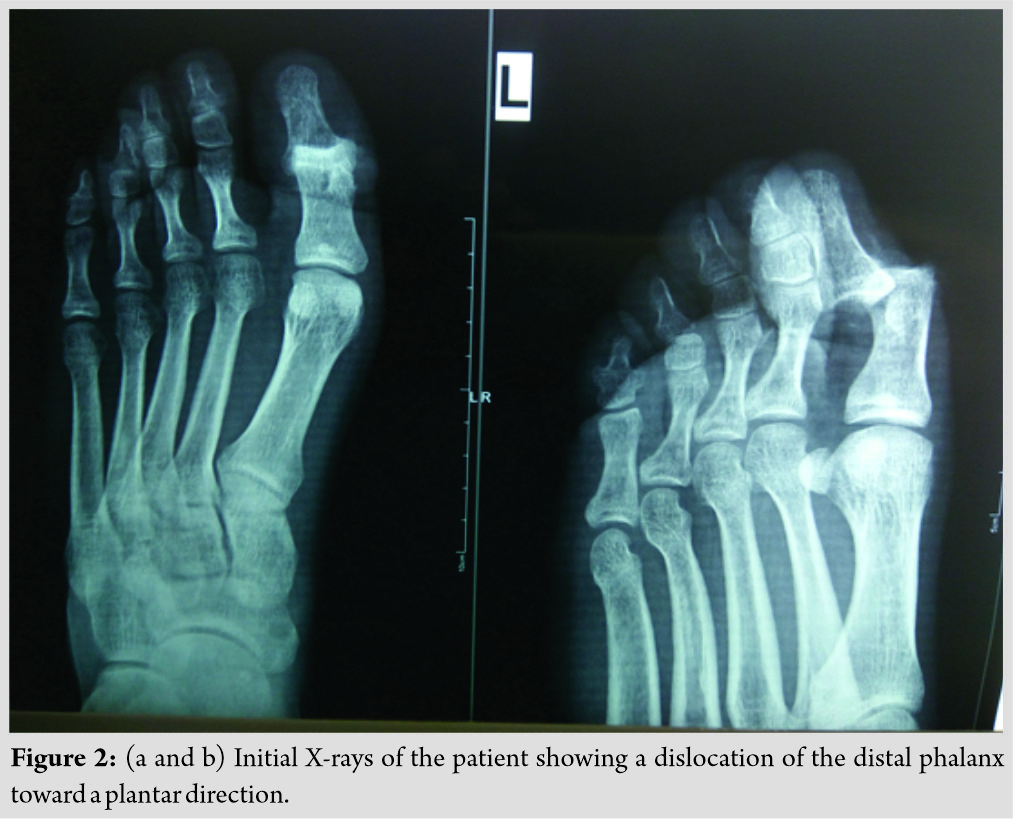

The patient underwent standard radiographic control (anteroposterior and lateral X-rays), which confirmed our clinical diagnosis (Fig. 2).